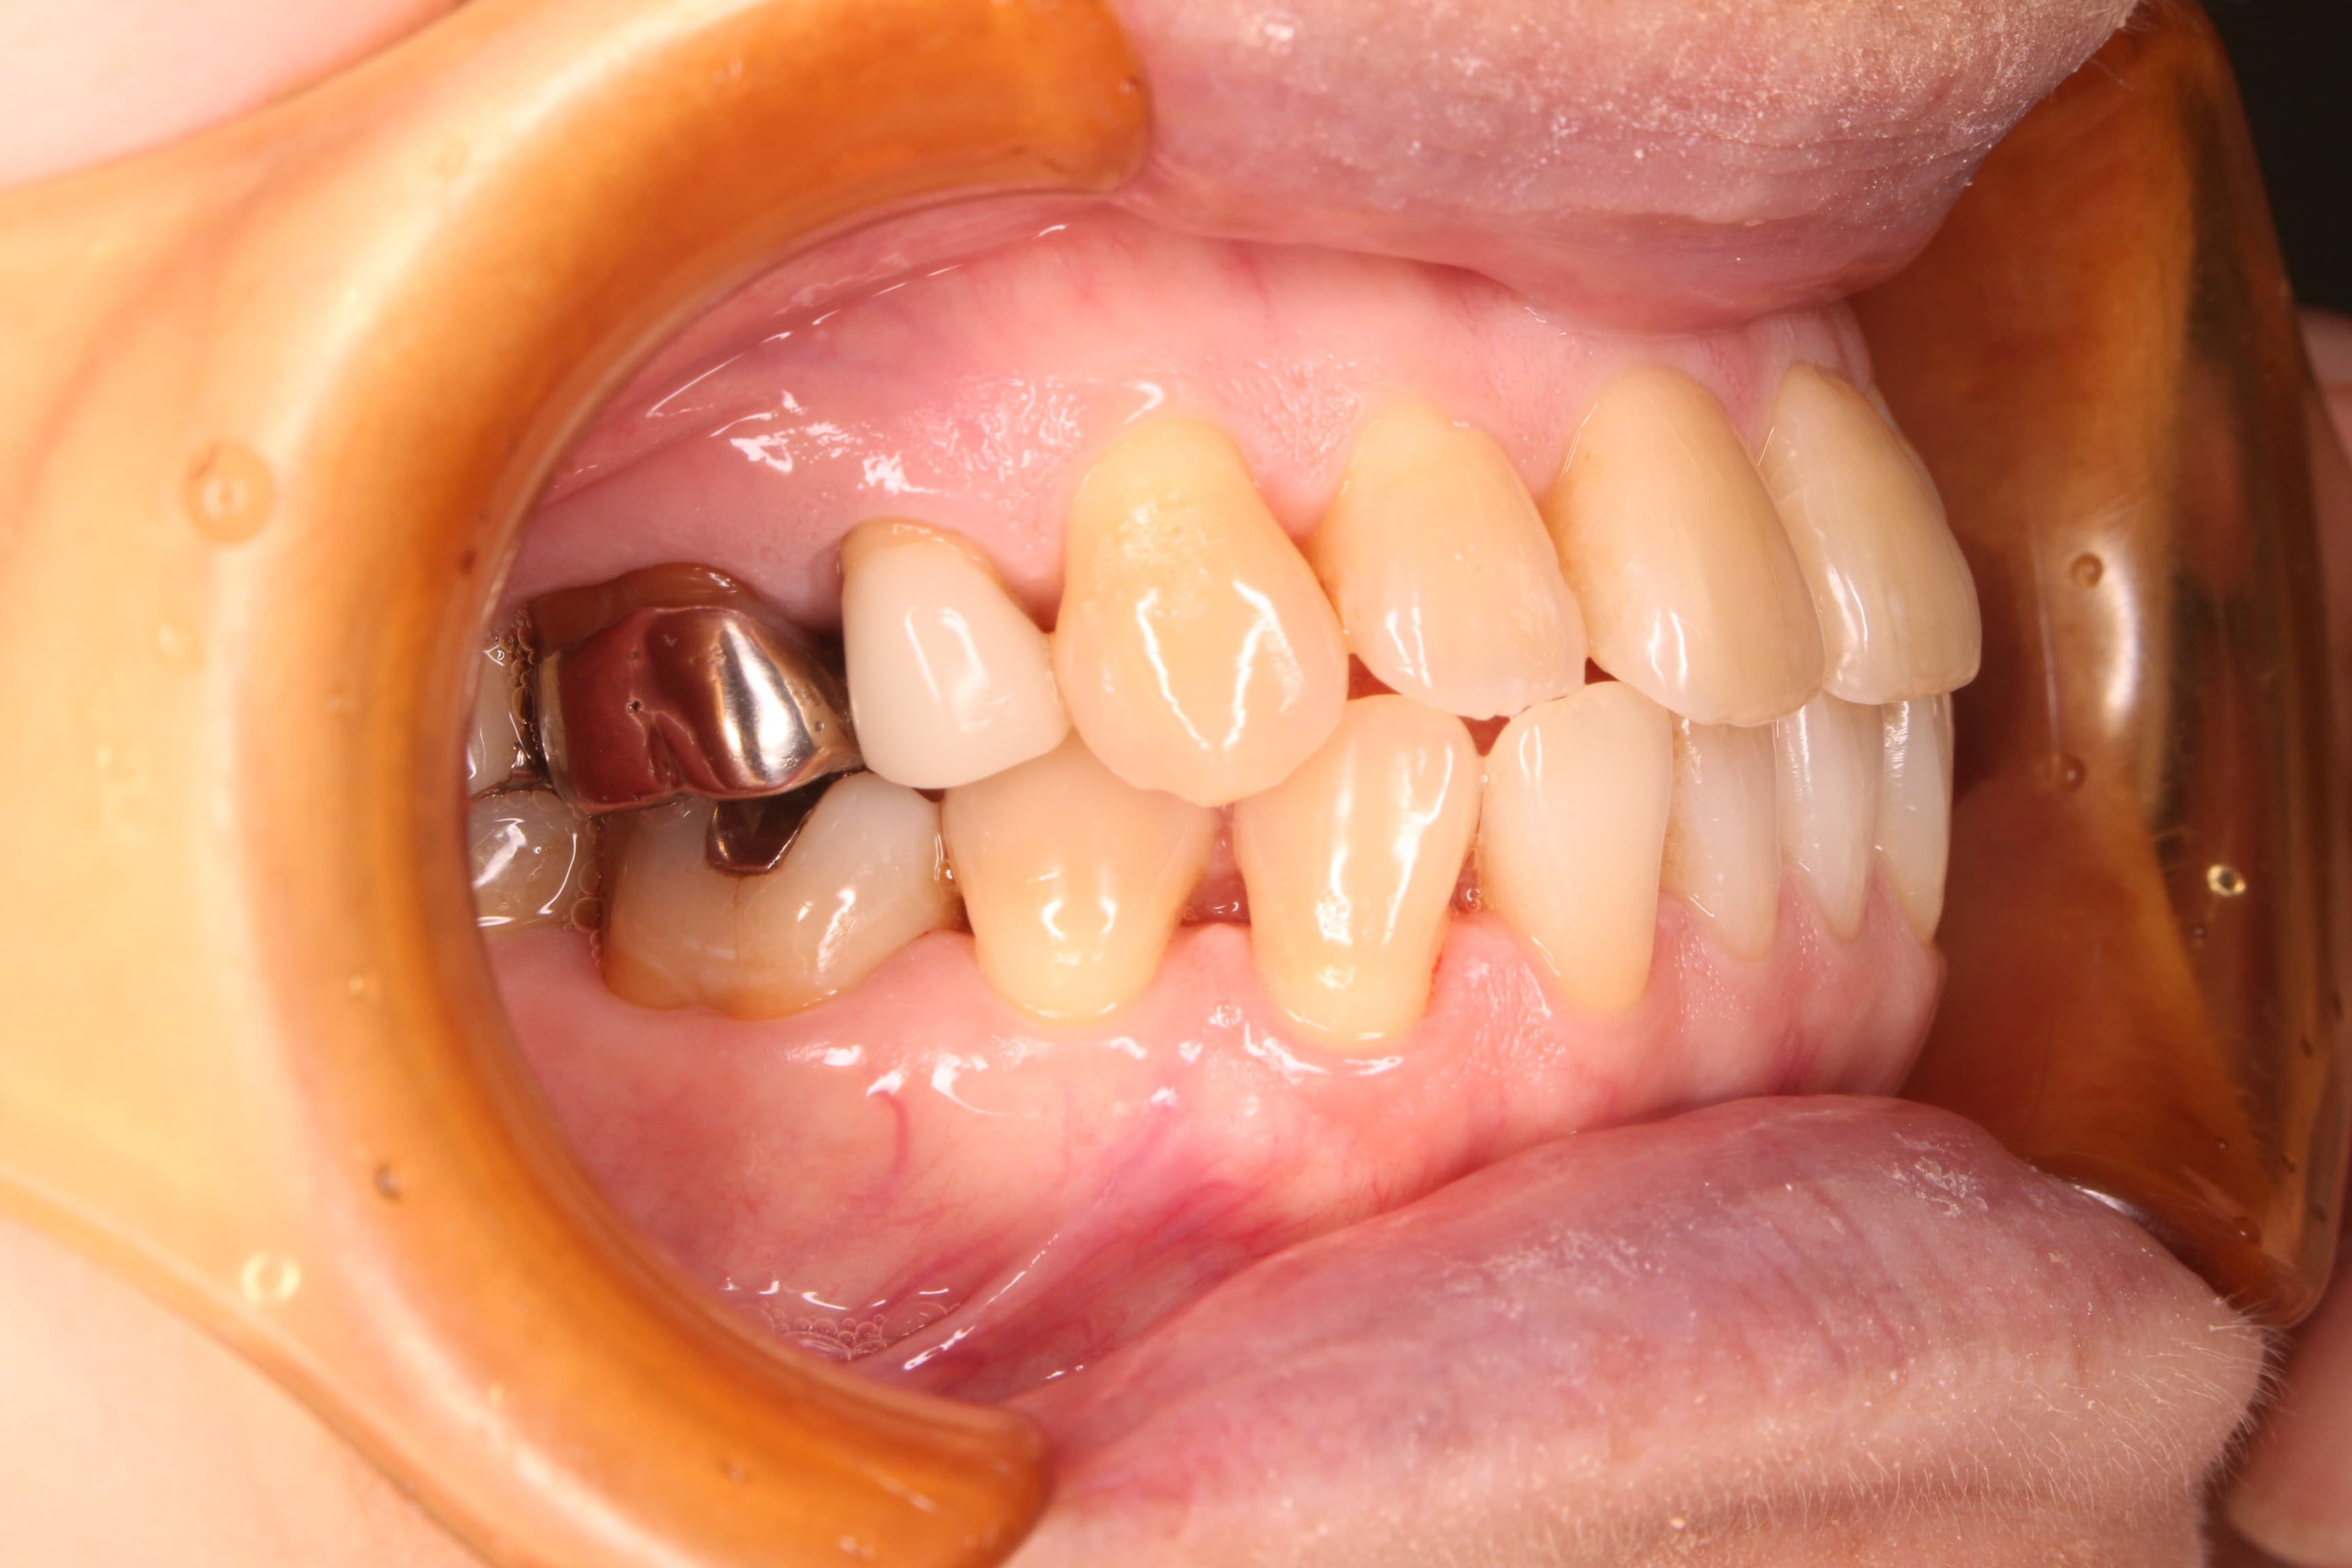

治療前

基本検査の結果、全体的に中程度の歯周ポケットがあり、歯肉からの出血、歯周ポケット内に歯石を確認することができました。

またお手入れは、ご自身では見え難いところに磨き残しがありました。